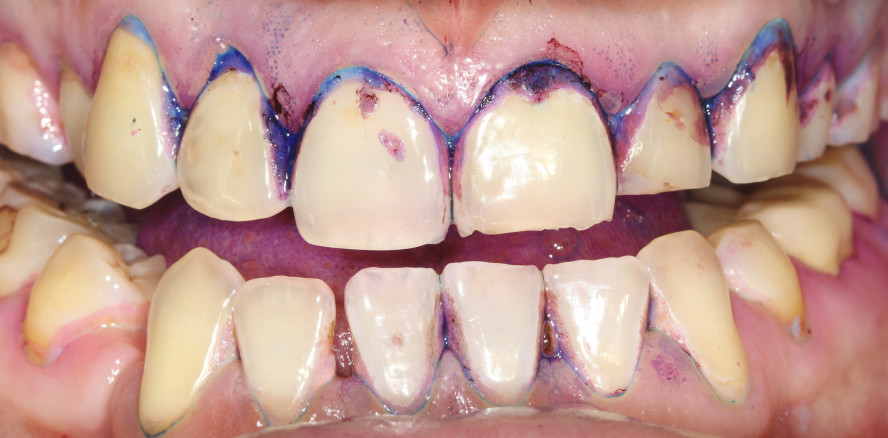

Für die eine erfolgreiche parodontale Prävention ist eine professionelle Instruktion der Patienten zu einem individualisierten Mundhygieneprogramm essenziell. Eine professionell durchgeführte Plaquekontrolle verbessert den Entzündungszustand der Gingiva und mindert die Plaquescores, ebenso bringt die individuelle Remotivation bei der oralen Hygiene dabei noch zusätzlichen Nutzen (Abb. 1). Dies erfordert allerdings einen erheblichen Zeitaufwand vom zahnärztlichen Team und dem Patienten.

Unabdingliche Voraussetzung für die individualisierte Plaquekontrolle ist die zahnärztliche Befunderhebung, patientenspezifische Analyse seiner Risikofaktoren, die Motivation und das Wiederholen der Empfehlungen sowie fortwährende Remotivation. Patienten müssen verstehen, dass parodontale Prävention einen lebenslangen Einsatz erfordert und dass der Weg zum Erfolg in der Zusammenarbeit mit dem zahnärztlichen Team liegt.